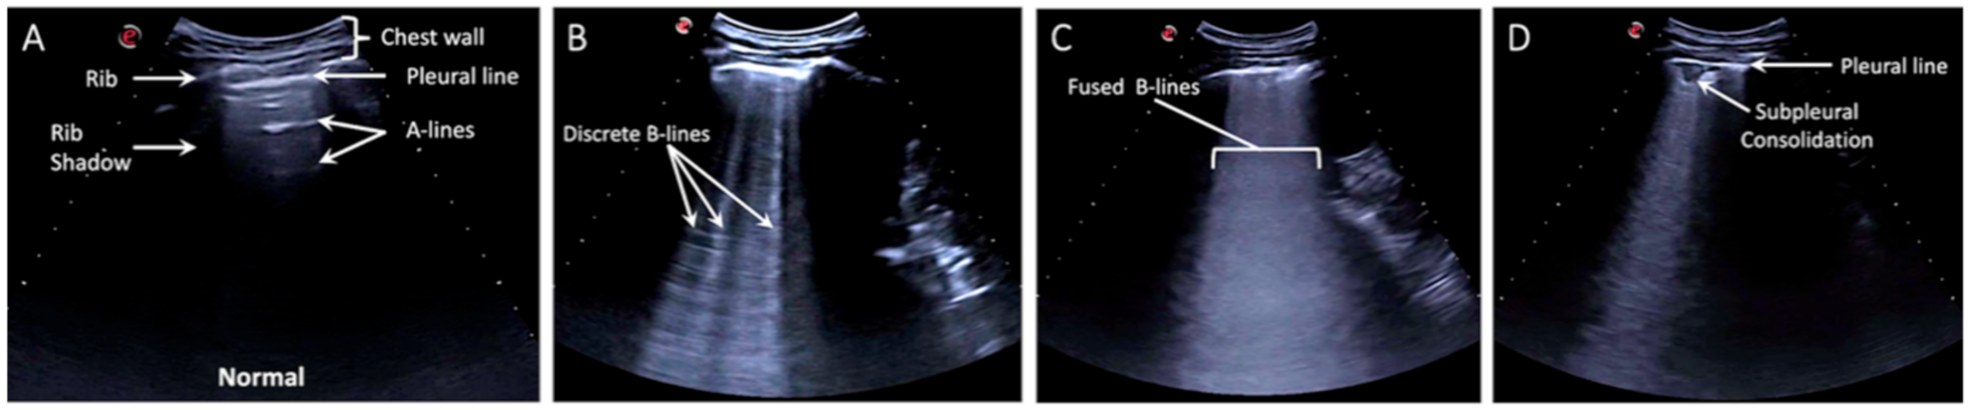

| Lung Ultrasound Findings | ||||

| Normal | 16 (30.2) | 2 (4.7) | 18 (18.8) | 0.001 |

| Discrete B-lines | 37 (69.8) | 41 (95.3) | 78 (81.3) | 0.001 |

| Confluent B-lines | 19 (35.8) | 29 (67.4) | 48 (50.0) | 0.002 |

| Small Subpleural Consolidations (<3 cm) | 18 (34.0) | 23 (53.5) | 41 (42.7) | 0.054 |

| Large Consolidations (>3 cm) | 2 (3.8) | 0 | 2 (2.1) | 0.198 |